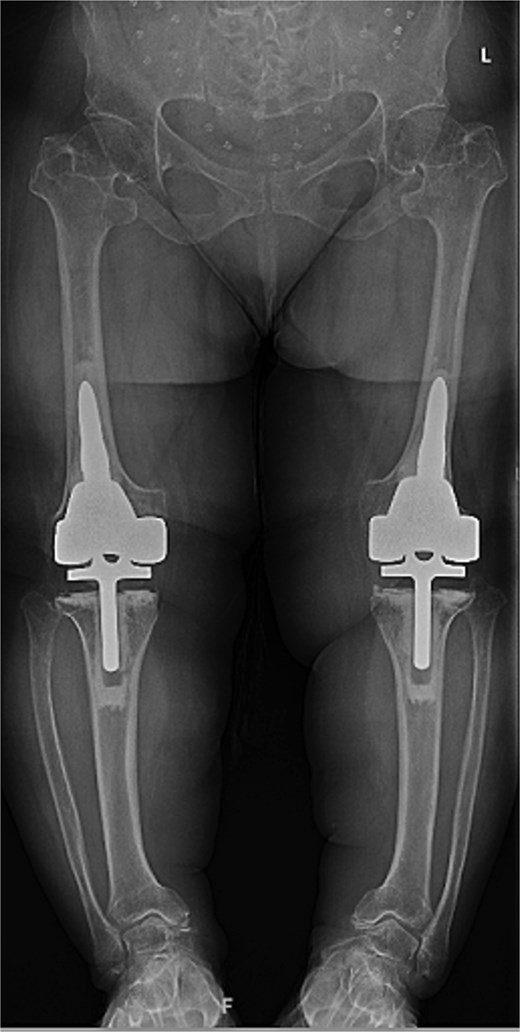

Given the severity of the coronal deformity, ligamentous laxity, and the patient’s functional limitations, the decision was made to proceed with simultaneous bilateral robot-assisted TKA using constrained prostheses. Using robotic-assisted navigation (Stryker Mako™), bony landmarks and soft tissue gaps were registered on the right knee. Initial preparation for a posterior-stabilized implant demonstrated profound lateral laxity after medial releases, prompting intraoperative conversion to a rotating-hinge design. A size XS femoral component and pediatric all-polyethylene tibial component (8 mm) were cemented, followed by hinge assembly. A similar approach was used for the left knee as severe medial compartment collapse and lateral laxity again necessitated the use of a rotating-hinge construct. The femur was prepared for an extra-small femoral component with a 12 × 50 mm cemented stem, and a size 8 mm pediatric all-polyethylene tibial component was implanted. The post-operative mechanical axis for the left and right knees were 4 and 6 degrees, respectively (Fig. 2).

Immediate postoperative AP radiographs following bilateral robot-assisted rotating-hinge TKA, showing well-aligned prosthetic components and correction of the coronal deformity. The post-operative mechanical axis for the left and right knees were 4 and 6 degrees, respectively.